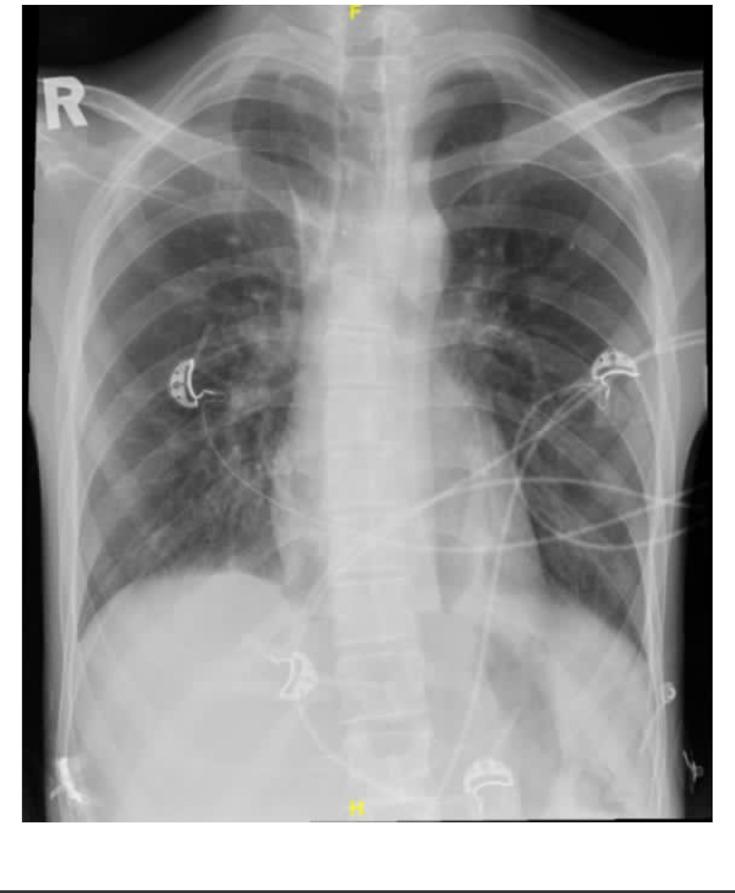

We report case of a 22-year-old male who was known to have temporal lobe epilepsy and mental retardation. He presented with status epilepticus. He was sedated and put on mechanical ventilation. Two days later, he developed a fever associated with increased tracheobronchial secretions and new infiltrates on chest X-ray. Diagnosis of VAP was made. Upon improvement, he was extubated and shifted out of ICU. Ten days after the onset of fever, he developed gradual onset bulbar weakness and ataxia. On examination, he had generalized areflexia and ataxia. CSF analysis showed cytoalbuminic dissociation. Antibodies against ganglioside complex were elevated. Diagnosis of sero-negative MFS was made, and intravenous immunoglobulin (IVIG) was started. He improved remarkably within two days.

我们报告一例22岁男性病例,该患者已知患有颞叶癫痫和智力障碍。他出现癫痫持续状态。给予镇静并进行机械通气。两天后,他出现发热,伴有气管支气管分泌物增多及胸部X线出现新的浸润影。诊断为VAP。病情好转后,他拔除气管插管并转出重症监护病房。发热发作十天后,他逐渐出现延髓性肌无力和共济失调。检查发现他存在全身无反射和共济失调。脑脊液分析显示蛋白细胞分离。抗神经节苷脂复合物抗体升高。诊断为血清阴性MFS,并开始静脉注射免疫球蛋白(IVIG)。两天内他病情显著改善。